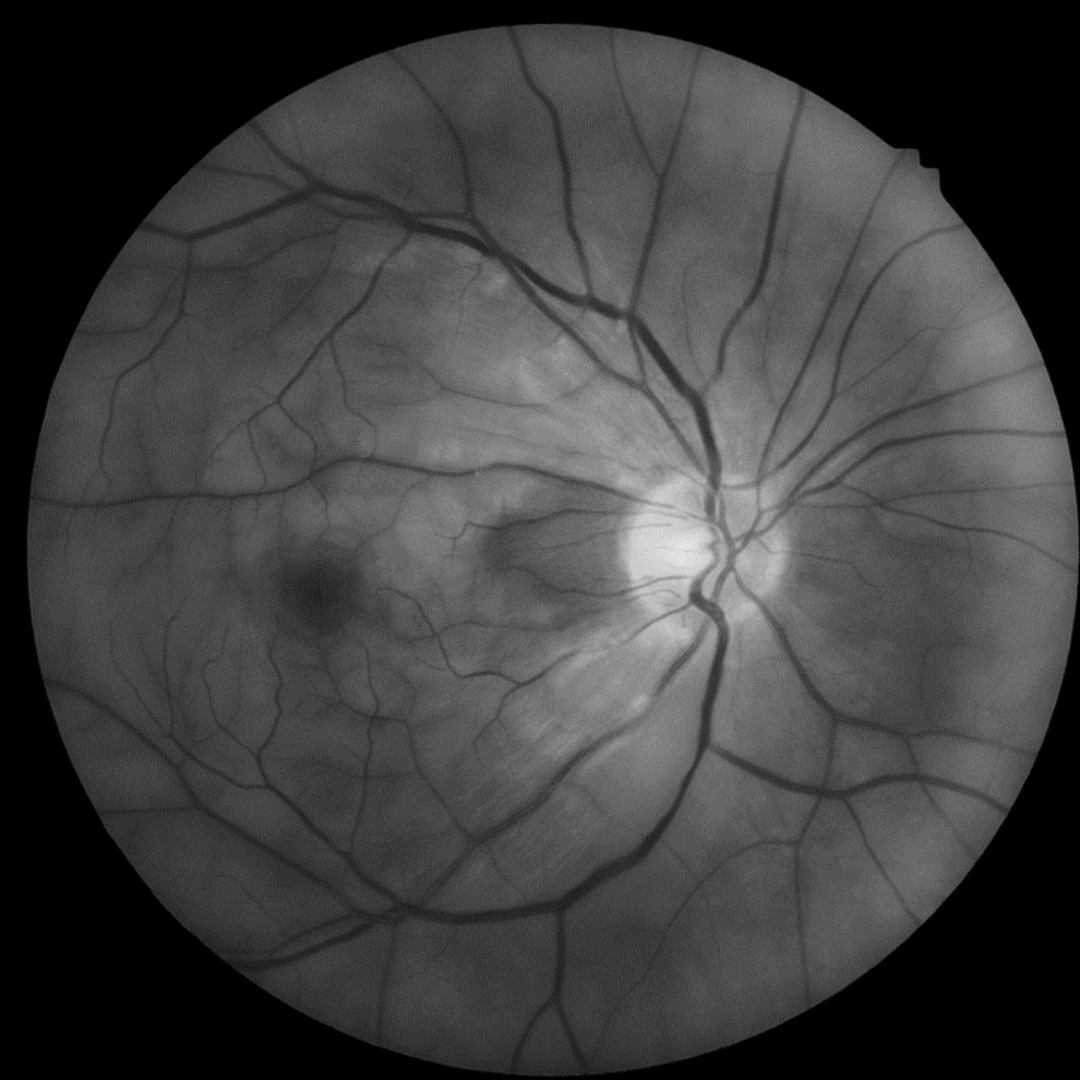

A 66-year-old Caucasian male with a sudden loss of vision in the right eye. He was diagnosed with a central retinal artery occlusion by an ophthalmologist. Images from a one-month follow-up appointment have also been included.

Fundus photography and red free image (right eye) at initial presentation

A CRAO means that there is no oxygenated blood reaching the retina, so it quickly becomes ischaemic and swelling of the retinal nerve fibre layer ensues, causing most of the retina to appear white and opaque. The exception to this is the fovea which retains its normal red colour. This is due to the fact that the central macula is characterised by the foveal avascular zone. In this area, the inner retina is physiologically absent so the swelling and whitening of the RNFL does not affect this zone and the practitioner can visualise the normal red colour of the choroidal circulation (supplied by the posterior ciliary arteries rather than the central retinal artery).